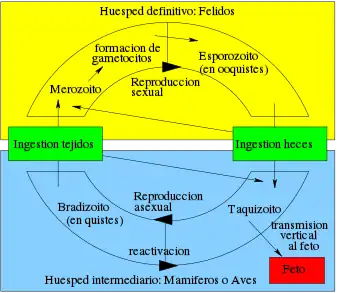

Ciclo de vida

El ciclo de vida del T. gondii tiene dos fases. La fase sexual del ciclo de vida ocurre solo en miembros de la familia Felidae (gatos domésticos y salvajes), haciendo que estos animales sean los hospedadores primarios del parásito. La fase asexual del ciclo de vida puede ocurrir en cualquier animal de sangre caliente, tales como otros mamíferos y aves. Por ello, la toxoplasmosis constituye una zoonosis parasitaria.[13]

Este protozoario puede infectar de tres formas por medio de:

Taquizoítos: encontrados en psedoquistes, estos son liberados de los bradizoítos y penetran cualquier célula infectandola hasta morir.

Bradizoítos: estos entran en forma de quiste al hospedero, donde pueden liberar taquizoítos o en el caso de hospederos de la familia Felinidae, pueden formar gametos para después conformar un ooquiste.

Ooquiste: esta última forma de infección solo es producida en los hospederos de la familia Felinidae, pues solo es estos se puede llevar a cabo el ciclo sexual del protozoario. Estos se forman a partir de los gametos femeninos y masculinos que nacieron de los bradizoítos. En estos se encuentran 2 sacos con 4 taquizoítos cada uno y son liberados en las heces.

La forma de infección se puede dar desde consumir agua o alimentos que estén infectados con el protozoario, hasta la ingesta de carne con quistes o pseudoquistes.[14]

En el hospedador intermediario, incluyendo los felinos, los parásitos invaden células, formando un compartimento llamado vacuola parasitófora[15] que contienen bradizoitos, la forma de replicación lenta del parásito.[16] Las vacuolas forman quistes, en especial en los músculos y cerebro. Debido a que el parásito está dentro de las células, el sistema inmunitario del hospedador no detecta estos quistes. La resistencia a los antibióticos varía, pero los quistes son difíciles de erradicar enteramente.

T. gondii se propaga dentro de estas vacuolas por una serie de divisiones binarias hasta que la célula infestada finalmente se rompe, liberando a los taquizoitos. Estos son motiles, y la forma de reproducción asexual del parásito. A diferencia de los bradizoitos, los taquizoitos libres son eficazmente eliminados por la inmunidad del hospedador o huésped, a pesar de que algunos logran infectar otras células formando, manteniendo así el ciclo de vida de este parásito.

Los quistes tisulares son ingeridos por el gato al alimentarse de un ratón infectado. Los quistes sobreviven el paso por el estómago del gato y los parásitos infectan las células epiteliales del intestino delgado en donde pasan por la reproducción sexual y la formación de ooquistes, que son liberados con las heces. Otros animales, incluyendo los humanos ingieren los ooquistes (al comer vegetales no lavados adecuadamente) o los quistes tisulares al comer carne cruda o cocida inapropiadamente. T. gondii puede infectar cualquier tipo de células del huésped, con excepción de los eritrocitos; lo anterior lo realiza mediante acción enzimática o dejándose fagocitar.[cita requerida]